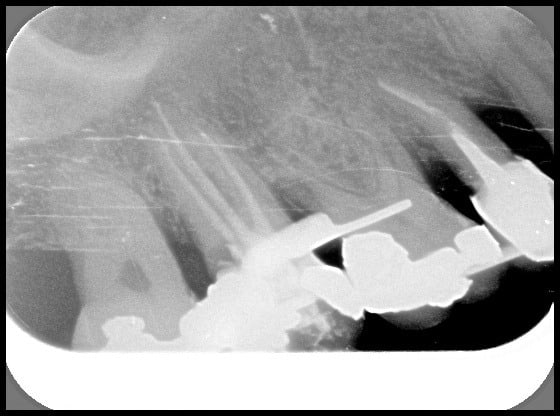

pendant que vous vous la pétez aux Seychelles (pffff) je me la pète au Termafil :-) héhé

c'est un bout de lime en mesial de la 46, a mi hauteur?

ben non, c'est le Thermafil....

hall,on s'en fiche:c'était là avant sur la radio de depart,elle a pu instrumenter et désinfecter au delà,l'obturation l'a englobé,dc tout va bien

Donc je ne la feliciterai pas pour etre passée a coté d'un morceau cassé.)

Désolé Doc , mais c'est Ploc qui veux pas... moi je voulais...;)